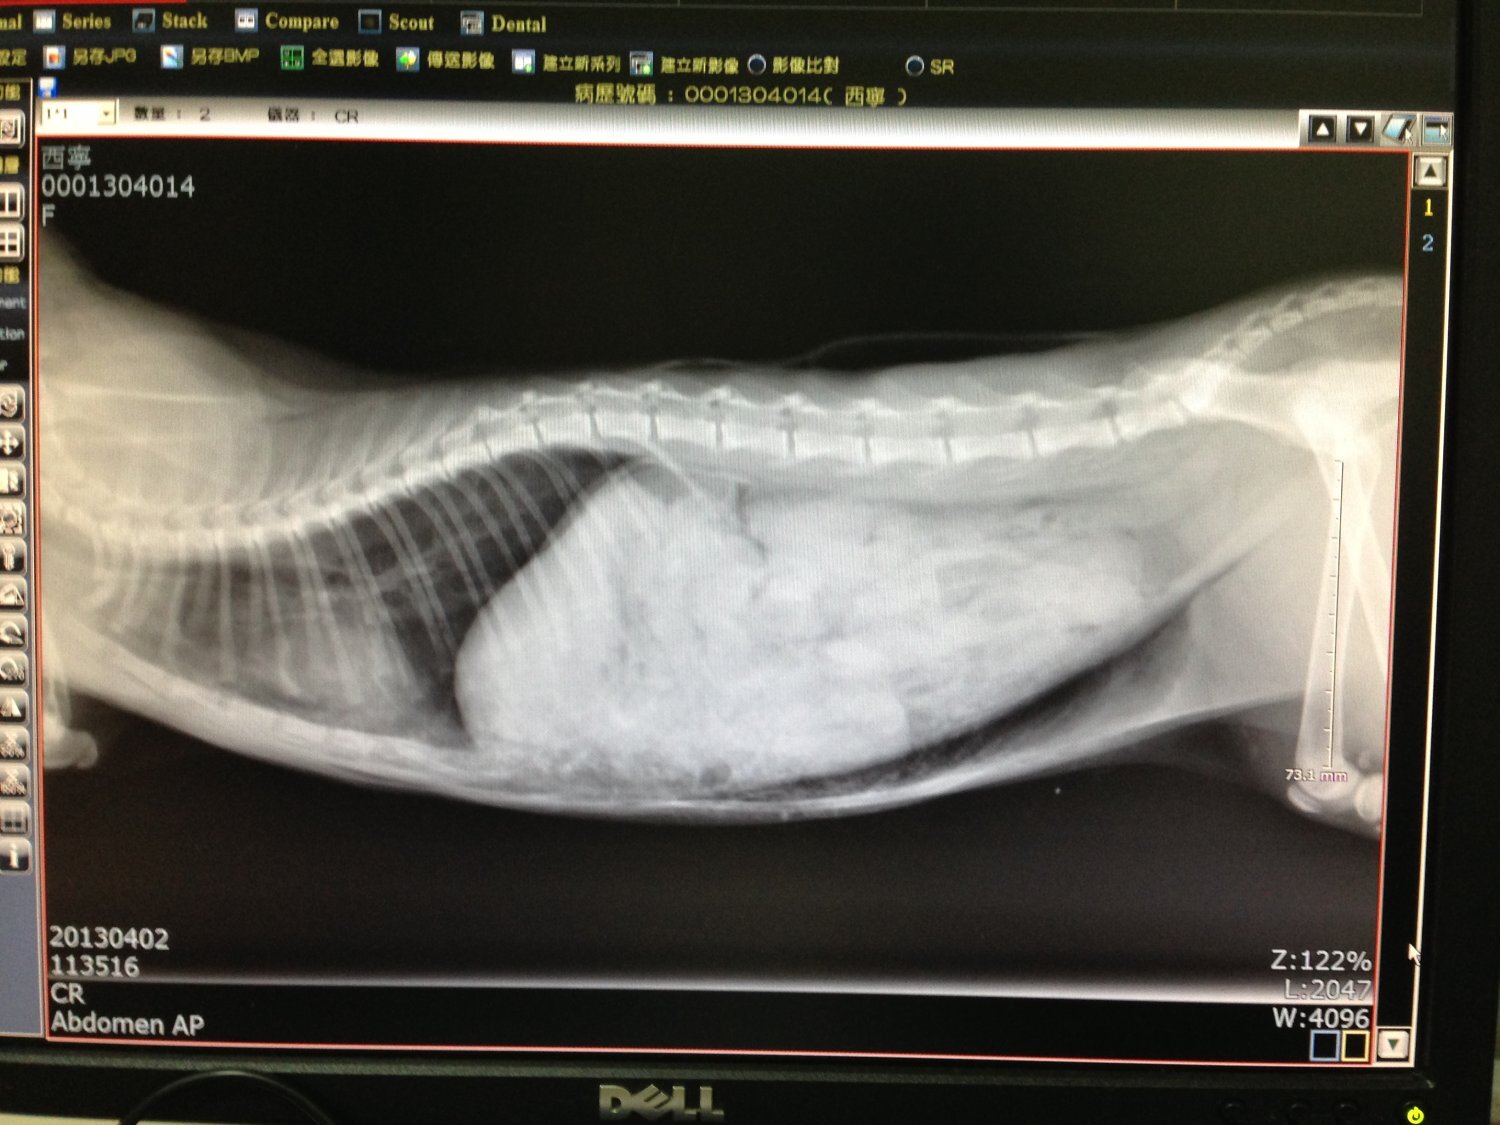

主題: 來不及長大的西門町路倒小貓 申請者姓名: 臺北市支持流浪貓絕育計劃協會 花色: 申請日期: 2013-04-11 17:55:19 申請者部落格: https://www.facebook.com/SupportTNR 申請者臉書網址: 所在縣市/合作醫院: 台北市/長青動物醫院 治療費用: 4950元 需求人數: 11人 已結案 (2013-08-06 14:21:45) 報名人員: Jolie Lin、TOM WANG(已付款)、Chloe(已付款)、Winnie Chen x2(已付款)、貓兔(已付款)、Jamie(已付款)、Vincent Ho(已付款)、林雅雯(已付款)、ailsa x2(已付款)、Yumi Yu(已付款)、 候補人員: 陳信良、 動物病情說明: 經粉絲團通報,一幼貓於西寧南路熱鬧的西門町,一間商店的門口,無法自己移動,志工前去救援。

送到醫院後,貓己非常虛弱,經初步檢查,小貓並無明顯外傷,X光顯示,腹部似乎有受到撞擊,而有腫脹的現像,經過醫院搶救,仍然無法救回小貓一命,於下午死亡,並由醫院安排,幫小貓火化。